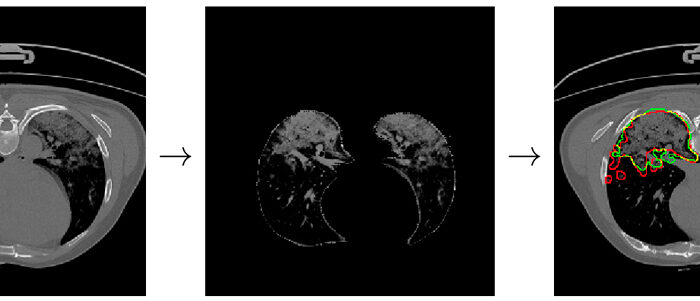

New system powered by deep learning makes it possible to detect Covid-19 lesions by analysing CT chest scans

Researchers at the Eurecat technology centre, the Computer Vision Centre (CVC) and the University of Barcelona (UB) have developed an [...]

MWC showcases a new system using artificial intelligence to spot nodules indicative of potential lung cancer

At this year’s Mobile World Congress, the Eurecat technology centre is showcasing a new system for identifying nodules which are indicators of [...]